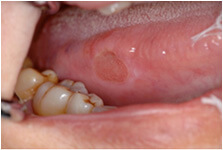

当科では初期の口腔がん(口の中にできる悪性腫瘍)の発見と早期治療に重点をおいています。口腔がんは早期発見・早期治療が重要であり、白板症や紅板症などの前癌病変が、明らかに悪性化する以前に検出可能な粘膜染色を応用し、早期発見・早期治療に努めています。また、悪性腫瘍切除に際しては、術中の迅速病理検査を行い、病理レベルで取り残しのない切除手術を行っています。

トルイジンブルー生体染色

トルイジンブルー染色液は青紫色の液体で、口腔粘膜に応用した場合、正常な粘膜上皮は染色されずに露出した腫瘍組織や異型上皮の細胞をメタクロマジー(胃染色性)によって染め分ける。

トルイジンブルーは発癌している部分に濃く青紫色に染色され、異型上皮には淡色する。

すなわち、ヨード不染部は口腔前癌病変が癌化に至るプロセスで、異型上皮が中等度から高度の段階で発現するのに対し、トルイジンブルー濃染部は高度から発癌の段階で発現するものと考える。

ヨード・トルイジンブルー生体染色

ヨード不染部とトルイジンブルー染色部のそれぞれの発癌過程での染色性の差を利用した方法である。ヨード染色により癌とその周囲の異型上皮を描出して、病変の範囲を確定した後に、いったん脱色して、さらにトルイジンブルー染色を施し、発癌している部分だけを明確に染め分ける方法である。

染色だけで癌あるいは異型上皮と確定診断ができるまでではないが、最初に行うスクリーニングテストとしては大変有効な方法である。